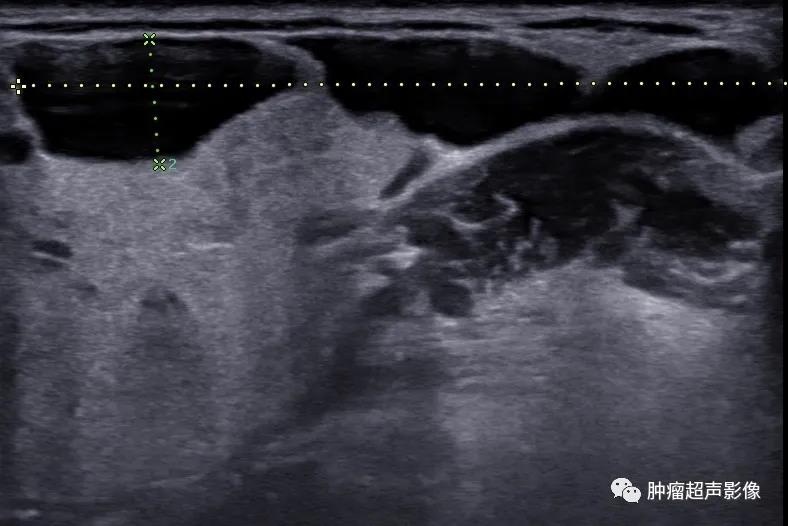

手术证实的口外型舌下腺囊肿:颌下区不规则无回声向口底部延伸,下颌舌骨肌有缺损,边缘毛糙,无明确的包膜,透声佳,无血流(来自微信好友会诊病例)。